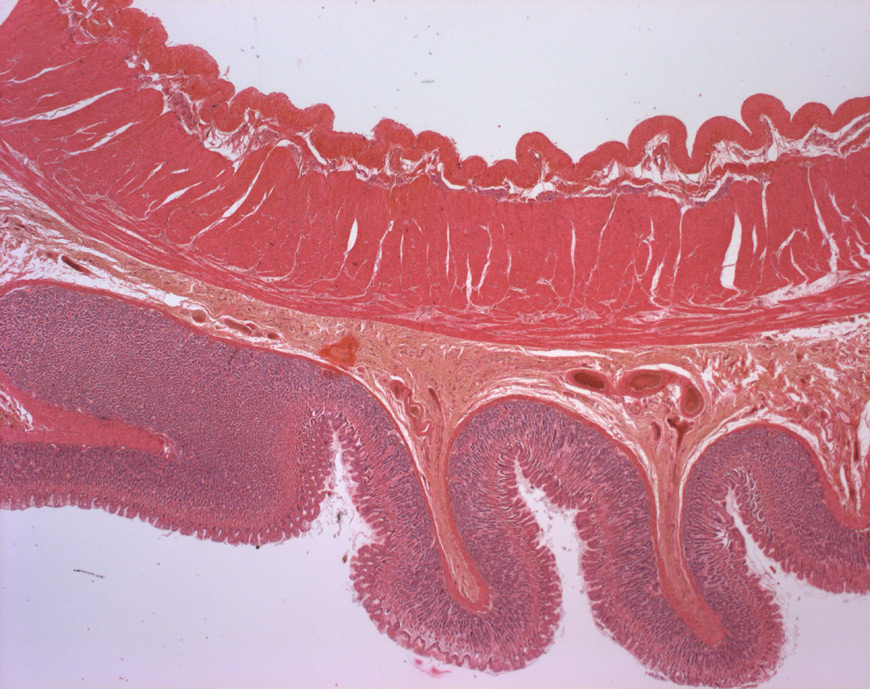

Der Magen besitzt den üblichen Aufbau aus Tunica mucosa, Tela submucosa und Tunica muscularis.

Charakteristisch für den Magenfundus/-Corpus findet sich hier in der Tunica Muscularis eine dritte innerste Muskelschicht, die Fibrae obliquae (scherengitterartig angeordnet)

Es wölben sich Plicae gastricae ins Magenlumen hinein, welche aus Tunica mucosa und Tela submucosa bestehen.

Diese Plicae wiederum besitzen selbst Einstülpungen, die Foveolae gastricae.

Die Tunica muscularis ist hier dreischichtig.

Neben der äußeren Längs- und der inneren Ringmuskulatur gibt es hier noch zusätzlich eine innerste Schicht, die Fibrae obliquae.

Zwischen Stratum circulare und Stratum longitudinale befindet sich der Auerbach-Plexus (oder Plexus myentericus).

In der Bildmitte: Tela submucosa.

Nach unten schließen sich an: Lamina muscularis mucosae, Lamina propria mucosae und Lamina epithelialis mucosae.

Nach oben die Tunica muscularis mit der innersten Schicht, den Fibrae obliquae.

Die Foveolae gastricae reichen als Glandulae gastricae fast bis zur Submucosa.